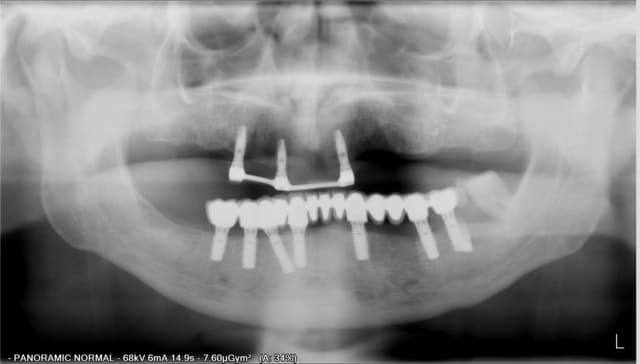

en haut,4 implant ont été posé en postextractionnel en vue d'une barre + stellite pano1.

L' implant en 21 à été perdu de façon précoce (avant mise en charge), mais la prothèse a tout de même été réalisée

en bas extraction du bloc antérieur + MCI (37 a été conservée)puis prothèse scellée au fujiplus sur pilier usiné.

Lors du controle à 1 an, on voit déjà une lésion autour de l'implant en 13.

Désolé mais les pano ne se sont pas mise dans l'ordre chronologique

En fait la plus récente est celle de gauche, et effectivement sur la plus a droite le patient a bougé